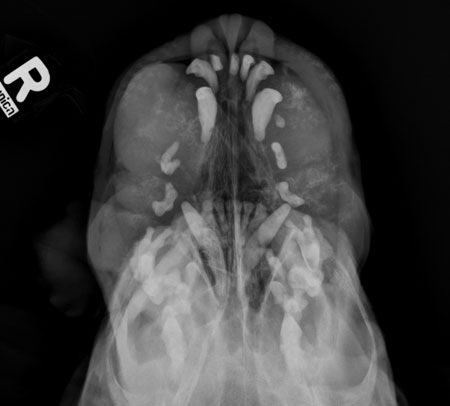

The reader tip will help you protect your dental digital radiography sensors.